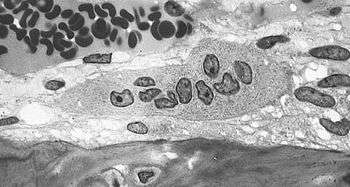

Light micrograph of an osteoclast displaying typical distinguishing characteristics: a large cell with multiple nuclei and a "foamy" cytosol.

The underlying mechanism in all cases of osteoporosis is an imbalance between bone resorption and bone formation. In normal bone, matrix remodeling of bone is constant; up to 10% of all bone mass may be undergoing remodeling at any point in time. The process takes place in bone multicellular units (BMUs) as first described by Frost & Thomas in 1963.[74] Osteoclasts are assisted by transcription factor PU.1 to degrade the bone matrix, while osteoblasts rebuild the bone matrix. Low bone mass density can then occur when osteoclasts are degrading the bone matrix faster than the osteoblasts are rebuilding the bone.[75]

The three main mechanisms by which osteoporosis develops are an inadequate peak bone mass (the skeleton develops insufficient mass and strength during growth), excessive bone resorption, and inadequate formation of new bone during remodeling. An interplay of these three mechanisms underlies the development of fragile bone tissue.[26] Hormonal factors strongly determine the rate of bone resorption; lack of estrogen (e.g. as a result of menopause) increases bone resorption, as well as decreasing the deposition of new bone that normally takes place in weight-bearing bones. The amount of estrogen needed to suppress this process is lower than that normally needed to stimulate the uterus and breast gland. The α-form of the estrogen receptor appears to be the most important in regulating bone turnover.[26] In addition to estrogen, calcium metabolism plays a significant role in bone turnover, and deficiency of calcium and vitamin D leads to impaired bone deposition; in addition, the parathyroid glands react to low calcium levels by secreting parathyroid hormone (parathormone, PTH), which increases bone resorption to ensure sufficient calcium in the blood. The role of calcitonin, a hormone generated by the thyroid that increases bone deposition, is less clear and probably not as significant as that of PTH.[26]

The activation of osteoclasts is regulated by various molecular signals, of which RANKL (receptor activator of nuclear factor kappa-B ligand) (receptor activator of nuclear factor kappa-B ligand) is one of the best studied. This molecule is produced by osteoblasts and other cells (e.g. lymphocytes), and stimulates RANK (receptor activator of nuclear factor κB). Osteoprotegerin (OPG) binds RANKL before it has an opportunity to bind to RANK, and hence suppresses its ability to increase bone resorption. RANKL, RANK and OPG are closely related to tumor necrosis factor and its receptors. The role of the Wnt signaling pathway is recognized, but less well understood. Local production of eicosanoids and interleukins is thought to participate in the regulation of bone turnover, and excess or reduced production of these mediators may underlie the development of osteoporosis.[26]